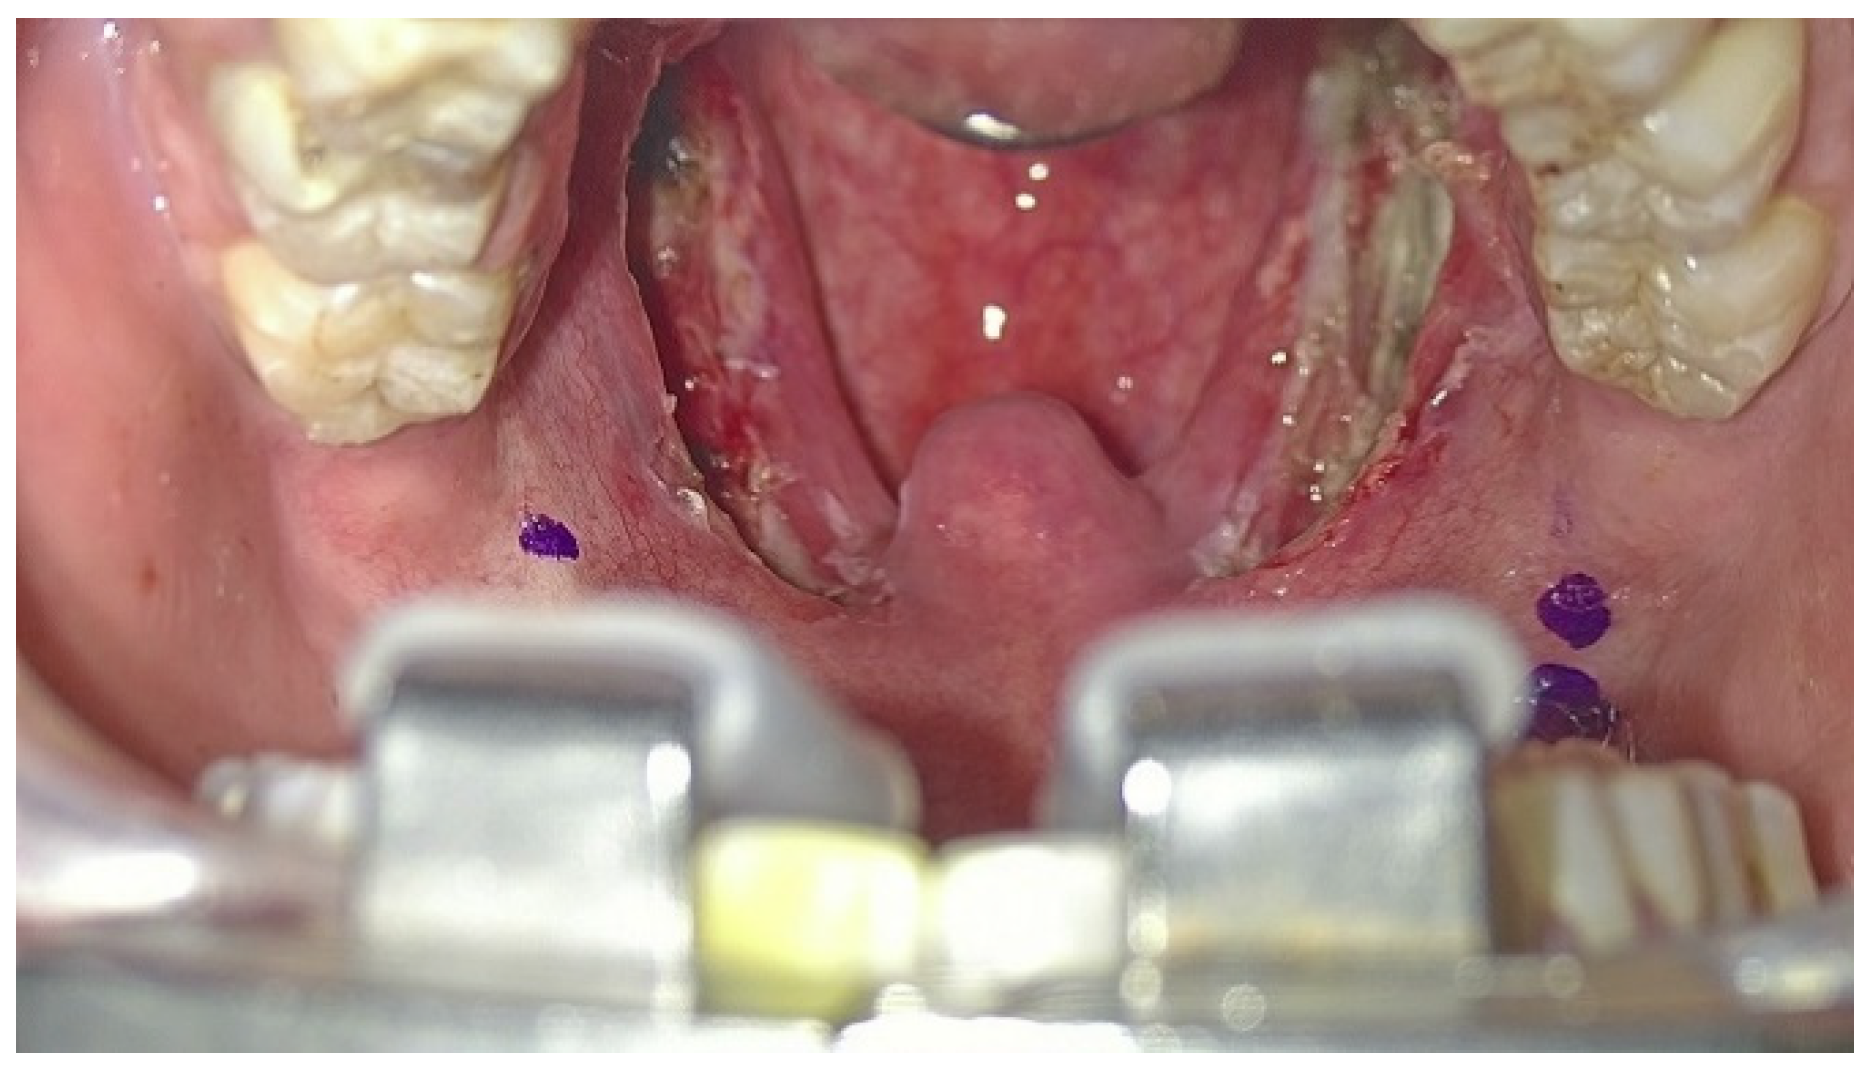

Patients underwent the ablation of 1 cm of tongue base lymphatic tissue on each side of the midline split (2 cm width and 1 cm depth of tissue ablation). The margins of resection include the anterosuperior sulcus terminalis, lateral amygdalo-glossus sulcus and posteroinferior glosso-epiglottic sulcus. Then, the ablation of each palatine tonsil was meticulously realized (Figure 3), sparing the palatopharyngeus muscles and the utmost mucosa covering both pillars in order to perform Barbed Reposition Pharingoplasty. The whole operating room team could see the surgical steps on 3D monitors (Figure 4).

Figure 3. Palatal operative field visualized with the exoscope: the first step of BRP surgery is tonsillectomy, saving as much of the muscular component of the lateral walls of the pharynx as possible.